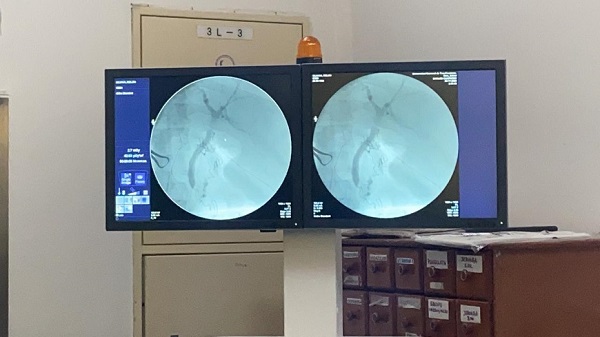

El Ministerio de Salud informó que se realizó con éxito la primera intervención quirúrgica con colangiografía intraoperatoria, herramienta utilizada para las patologías relacionadas a las vías biliares.

Con el dispositivo los médicos obtienen información sobre la morfología de las vías biliares, que es usado en una operación abdominal introduciendo contraste radioopaco, visto con rayos X, refiere el portal de la cartera sanitaria.

El procedimiento se llevó a cabo con el Equipo Radiológico Arco en C en el Hospital de Pedro Juan Caballero.